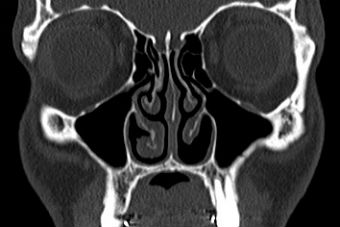

Doctors who treat empty nose syndrome. Oral Corticosteroids Following Endoscopic Sinus Surgery for Chronic Rhinosinusitis Without Nasal Polyposis. 21 Responses to Empty Nose Syndrome Doctors As a new entrant to the ENS sufferers worldI believe that the international society of otolaryngology shoUldale issue a statement banning any doctor from unilaterally deciding on any level of tampering with this very important part of the nostrils under any circumstances. It refers to the fact that a patients CT scan looks empty or devoid of normal tissue following nasal surgery specifically turbinate excision.

A totally avoidable physician-induced deformity resulting in an as-of-yet incurable and debilitating condition. Here is the modeled SMR I presented earlier as having normal pressure and resistance values on the pressure graphs. Empty Nose Syndrome ENS also known as the Syndrome of the Empty Nose occurs frequently after surgical procedures of the nose and is characterized by several symptoms such as respiratory impairment a dry nose and related inflammatory processesReduction of nasal conchae which are an internal structure of the nose or surgery of the nasal septum are.